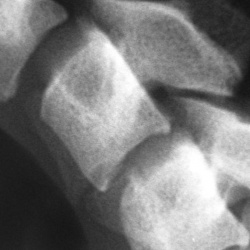

20.02.2014 - 11:41

При обследовании шейного отдела позвоночника (жалобы на сильнейшие простреливающие боли в левой руке, особ, пальцы, из покраснение, отек.....), на боковой рентгенограмме в проекции ...